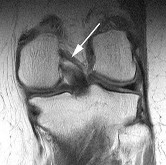

Figure 21 shows a coronal T1-weighted MRI scan of the knee. The arrow indicates what anatomic structure? ](http://www.orthobullets.com/anatomy/10120/medbullets-onboarding--draft-html)